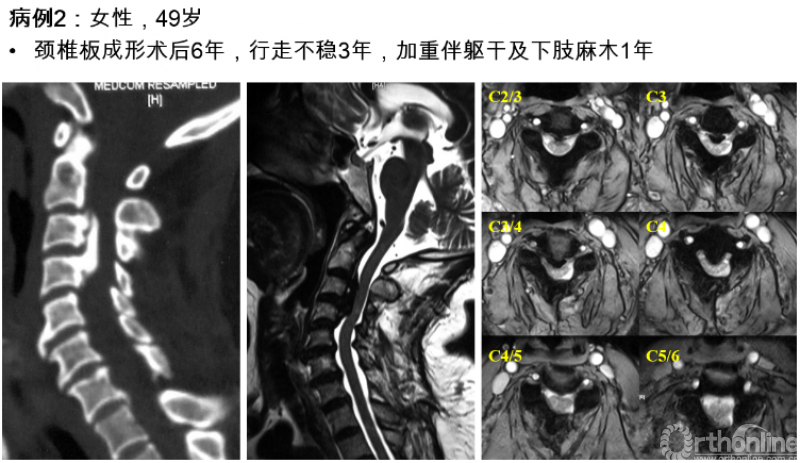

实际上,类似于病例1的情况并不少见,尤其多见于后纵韧带骨化症的患者,暂且不对例1的治疗方案做出决定,我们来看另一例给我们启示的病例:

图2

对于该例患者,C2/3间隙水平有轻度脊髓压迫,脊髓受压最重的节段仍然在C3/4水平。我们进行了再次手术,并向头侧扩大减压范围至C2,术后不仅C2/3水平的轻微压迫得到解除,C3/4水平脊髓压迫也明显去除了(图3),神经功能改善。

这个病例给我们的启示是:扩大减压范围至C2,有助于提高C3/4水平脊髓减压的效果。然而,显然并不是所有患者都需要扩大减压,那么需要回答的问题是:C3/4水平的脊髓前方致压物多大,需要扩大减压范围至C2?

图3 术后核磁显示脊髓减压充分